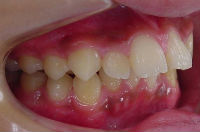

治療開始時 治療終了時

前歯の歯並びが乱れている子供の症例。<出っ歯> 医療法人社団 クオリタス いずみ歯科矯正歯科医院 (浦安市)

前歯の歯並びが気になり来院される患者さんが多いです。

出っ歯の位置を改善する事により

今回の症例は独自の方法とt4kなどによって改善しました。